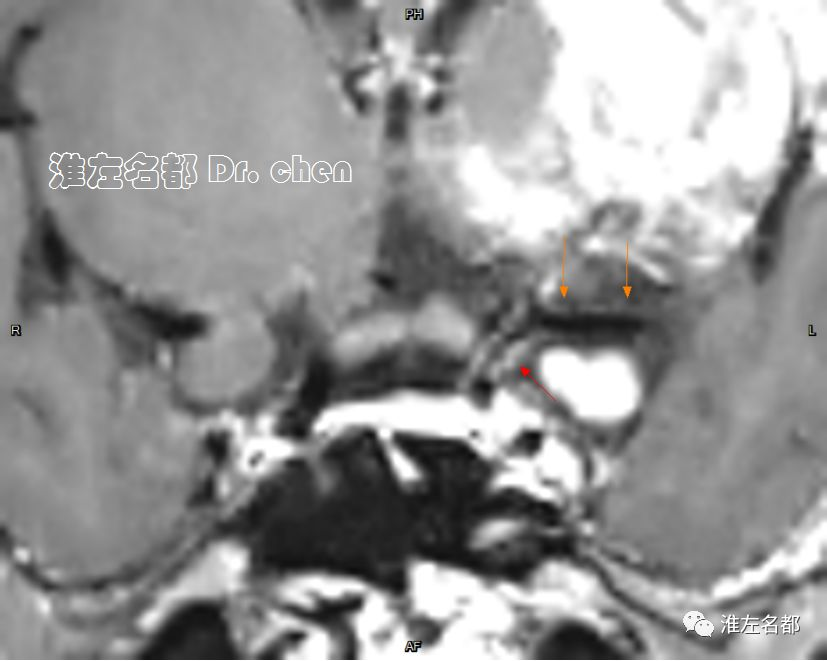

△管壁高分辨MRI(增强T1-SPACE):左侧大脑中动脉主干管壁未见异常(橙箭),左侧颈内动脉远端管壁增厚和强化(红箭)。

△管壁高分辨MRI(增强T1-SPACE):左侧颈内动脉末端检测到夹层“内膜征”(橙箭)。

3.脑动脉夹层临床确诊依赖于影像学检测到典型夹层征象:内膜征/双腔征、长段不规则/丝线样狭窄、壁内血肿、夹层动脉瘤等。本患儿DSA显示左侧颈内动脉末端和大脑中动脉主干长段狭窄,且大脑中动脉主干狭窄呈“丝线样”,符合夹层影像学征象。

6.在夹层真腔得以基本恢复后,DSA于左侧颈内动脉末端、大脑前和中动脉近端均检测到典型“内膜征”,进一步确定了夹层诊断。